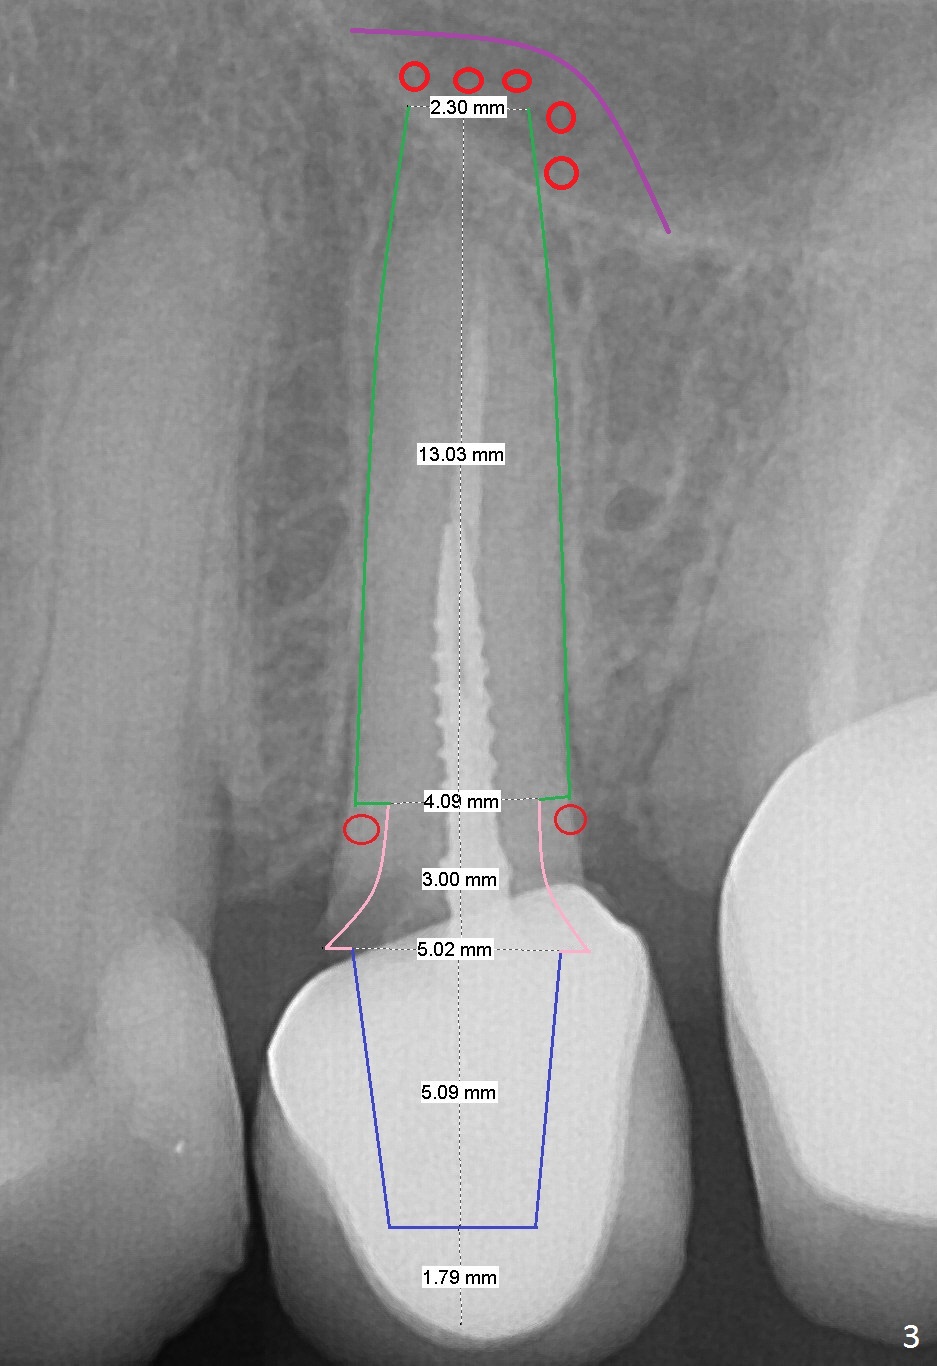

A 60-year-old woman returns to office with chief complaint "upper left crown is loose again". Clinical exam confirms #13 crown fracture at the gingival level (Fig.1,2 *). Since the native bone is short, an implant (Fig.3 green) should penetrate the sinus floor for primary stability. To protect the sinus membrane, PRF membranes (purple curved line) will be inserted prior to bone graft (red circles) and the implant. A pair abutment is expected to be 5x5 (5.7 exactly, blue) (Fig.3, pink) mm. The implant should be placed palatally to avoid buccal metal show through.